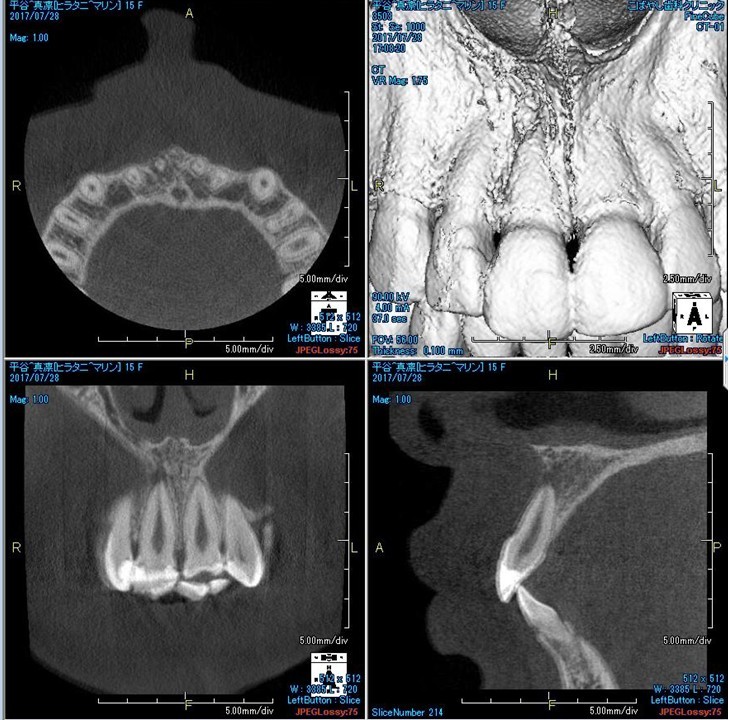

(図29)初診時のCBCT像

上1番の根尖周囲に透過性のレントゲン像が確認できる。唇側皮質骨の消失の可能性も予測でき、歯髄壊死の可能性が高いと考える

(図32)術後3ヶ月のCBCT像

根尖周囲組織の回復を認める

(図34)初診時と術後3ヶ月のCBCT像の比較

根尖部付近に明らかに変化が認められる特に根尖周囲の骨の回復が確認できる